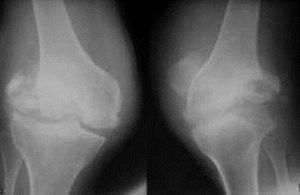

3.膝關節退行性病變

起病緩慢者膝關節疼痛不嚴重,可持續性隱痛,氣溫降低時疼痛加重,與氣候變化有關,晨起後開始活動,長時間行走,劇烈運動或久坐起立開始走時膝關節疼痛僵硬,稍活動後好轉,上、下樓困難,下樓時膝關節發軟,易摔倒。蹲起時疼痛,僵硬,嚴重時,關節酸痛脹痛,跛行,關節功能受限,以下蹲最為明顯,伸屈活動有彈響聲,部分患者可見關節積液,局部有明顯腫脹、壓痛現象,合併風濕病者關節紅腫、畸形。

4.X線平片

早期階段,X線片大多正常,中晚期可見關節間隙不對稱性狹窄、關節面下骨硬化和變形、關節邊緣骨贅形成,關節面下囊性變和關節腔游離體等。X線片可分為五級。0級:無改變;1級:輕微骨贅;2級:明顯骨贅,關節間隙正常;3級:骨贅外關節間隙中度狹窄;4級:骨贅外關節間隙嚴重狹窄,伴軟骨下骨硬化。